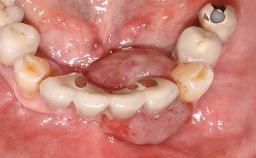

Implant Placement with Simultaneous Contour Augmentation using GBR

Surgical treatment of a 67-year-old male patient exhibiting an extended edentulous space in the anterior maxilla after the removal of three hopeless incisor teeth.

The case concludes with the presentation of the final prosthesis and the esthetic outcome, demonstrating stable soft tissue conditions and stable bone crest levels at the 3-year follow-up.